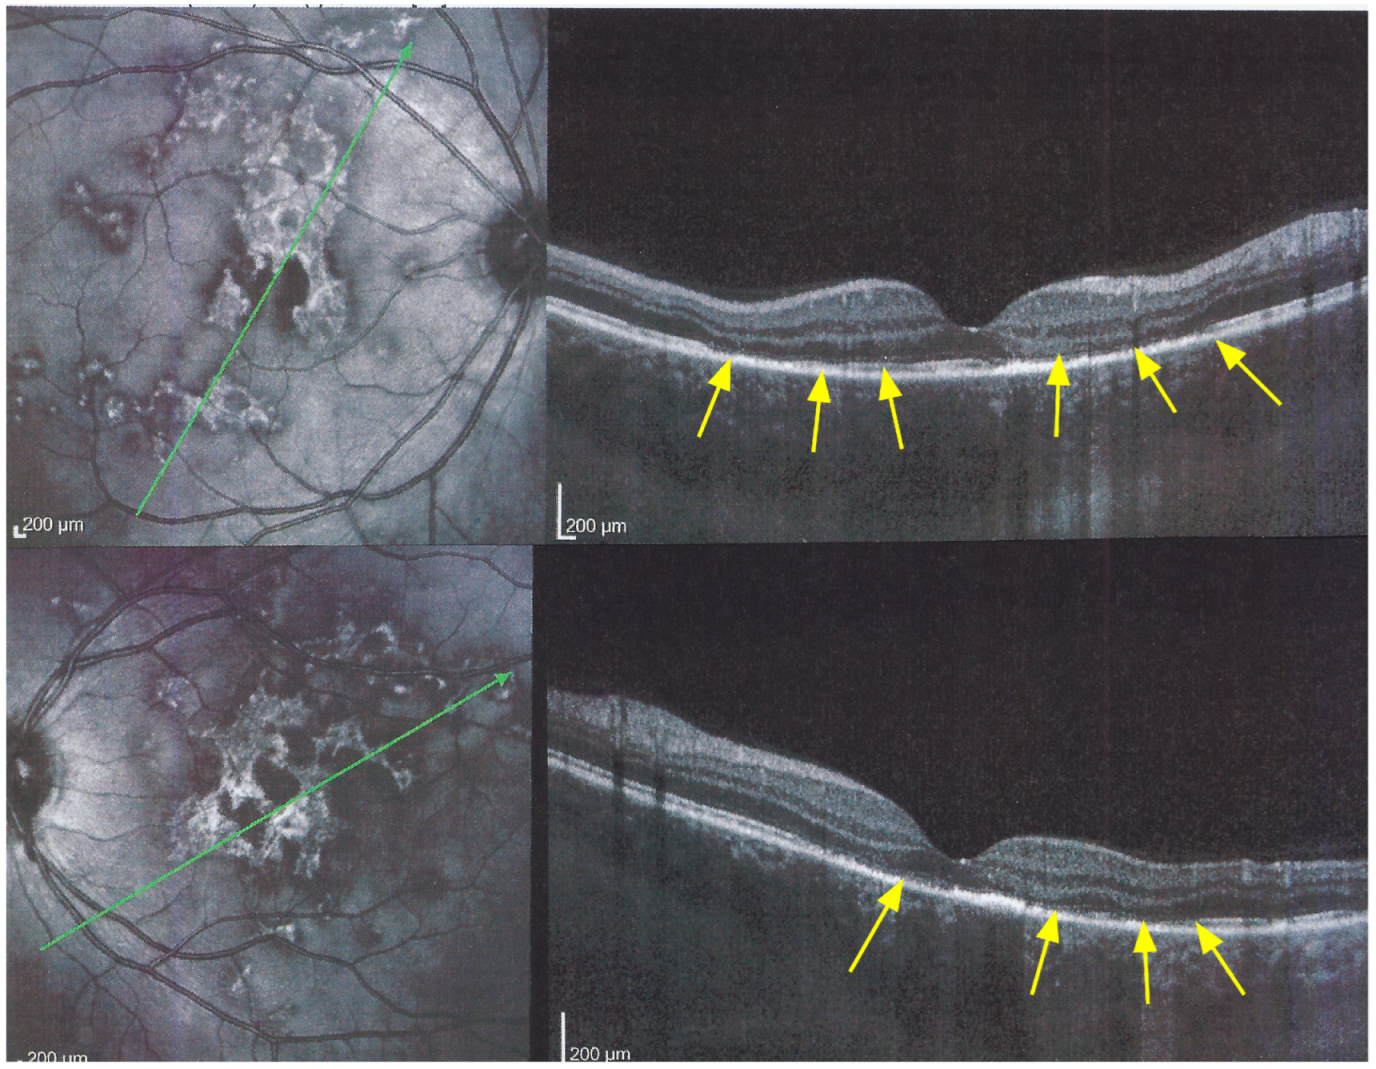

Figure 8. APMPPE/AMIC; SD-OCT in initial-acute phase OD (top) and OS (bottom) (same patient as Figure 5, Figure 6 and Figure 7a). In this initial phase, SD-OCT shows areas of hyperreflective changes visible in the outer plexiform layer and adjacent outer nuclear layer (arrows) but no loss of photoreceptor outer segments (see Figure 5).

Figure 9. APMPPE/AMIC; SD-OCT in subacute phase OD (top) and OS (bottom) (same patient as Figure 5, Figure 6, Figure 7a and Figure 8). In the subacute phase, SD-OCT shows extended areas of loss of photoreceptor outer segments (arrows) and thickened RPE, hyperautofluorescent on BL-FAF (see Figure 5).

The chorioretinal findings by spectral domain optical coherence tomography (SD-OCT) depend on the degree of involvement and the stage of the disease [5,7,25]. In early-acute disease ischaemia, induced by choriocapillaris non-perfusion, causes thickening of the outer retina including the IS/OS line and beyond (Figure 8). In later stages, SD-OCT can show either simple loss of photoreceptor outer segments, thickened RPE or atrophy with loss of RPE (Figure 9).

SD-OCT findings included thickened hyperreflective areas of the outer retina in the very early disease phase (10/35 eyes) (Figure 8 and Figure 11), photoreceptor outer segment loss and/or ellipsoid zone disruption-RPE alterations (22/35 eyes) (Figure 9), subretinal fluid (serous retinal detachment—SRD) (4/35 eyes), (Figure 14) and atrophy (3/35 eyes) in the late stage of the disease (Figure 15).